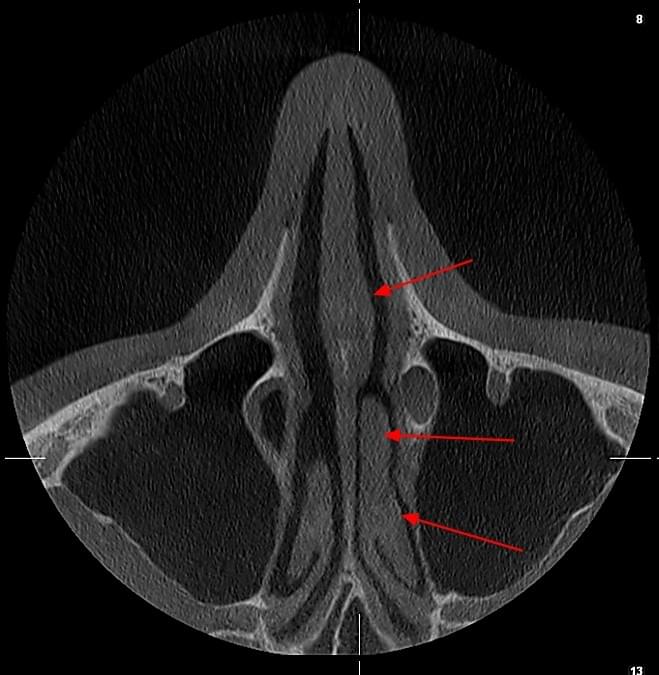

КПКТ (конусно-променева комп’ютерна томографія) — це 3D-знімок високої роздільної здатності. На відміну від звичайного рентгену, КТ показує: